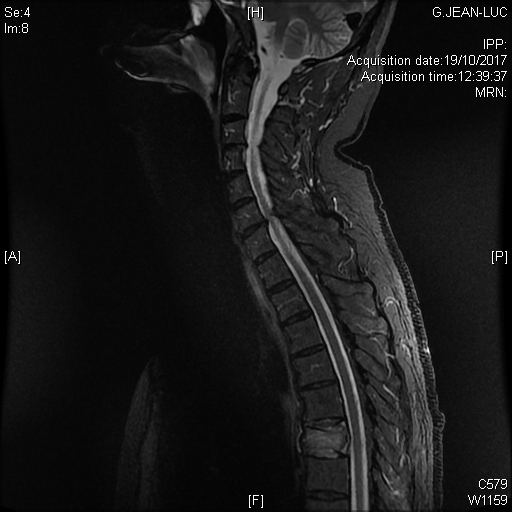

Tableau clinique de compression médullaire en rapport avec une hernie discale thoracique exclue